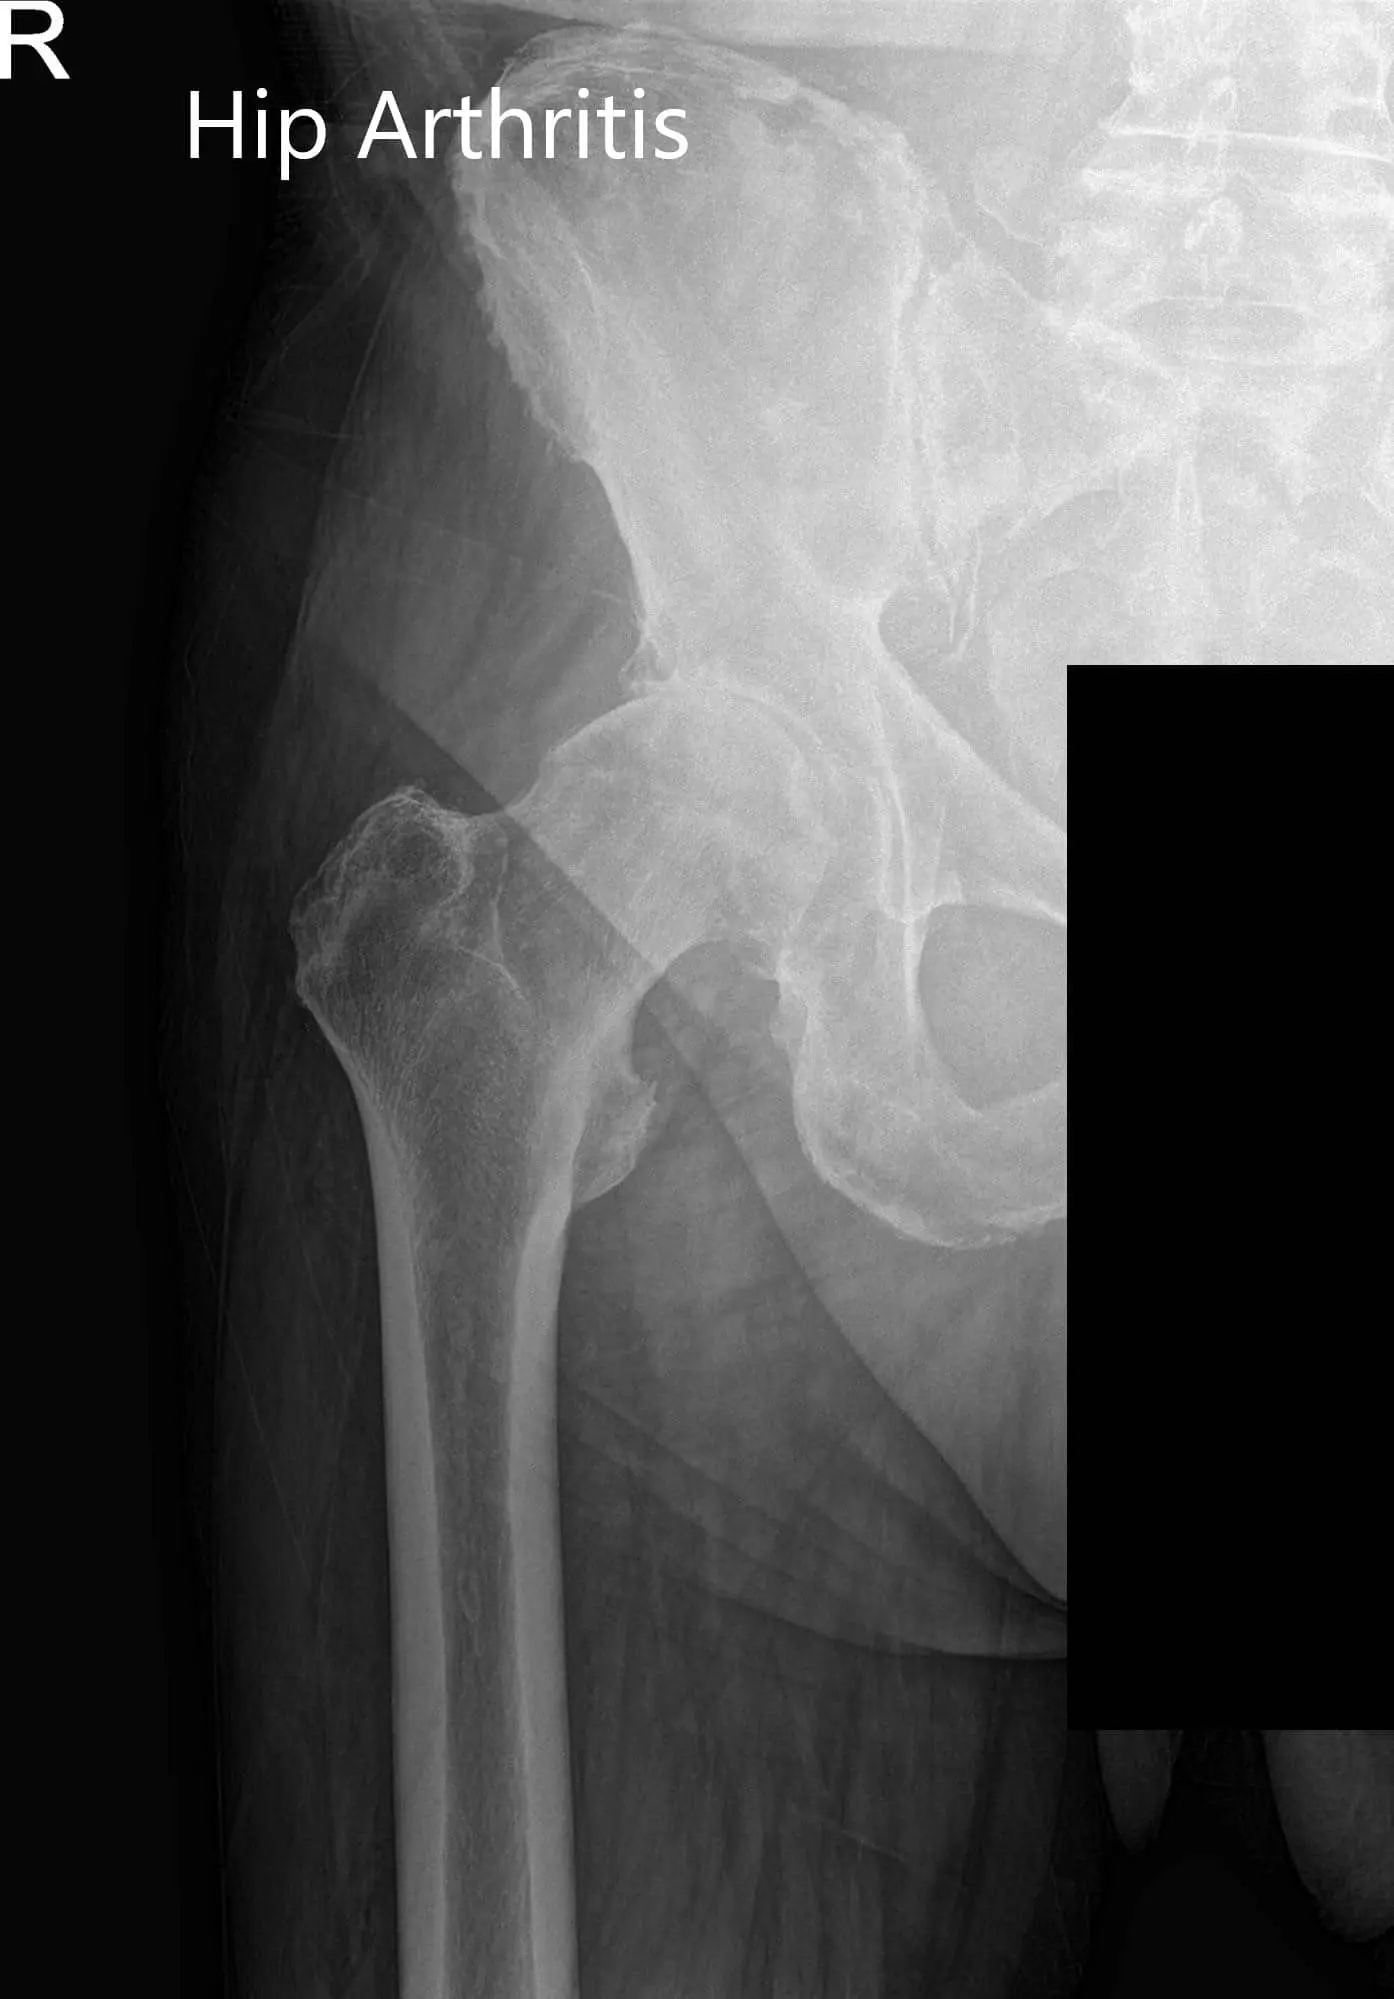

Radiographs of the pelvis revealed osteoarthritic changes in the right hip. Considering her comorbidities and lifestyle limiting hip pain, she was advised a total hip replacement surgery. She was made aware of the added risk of the surgery owing to atrial fibrillation and hypertension.

Preoperative X-ray images showing AP and frog-leg lateral view of the right hip - img 2

Preoperative X-ray images showing AP and frog-leg lateral view of the right hip